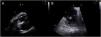

Lung nocardiosis was diagnosed and he was put on imipenem and trimethoprim-sulfamethoxazole. Despite effective treatment, the patient presented recurrent fever. Transesophageal echocardiography documented exuberant multinodular vegetations involving all cusps of the aortic valve (maximum width 10 mm×12 mm) (Figure 1A and B and Video 1), in a pattern resembling the Mercedes-Benz symbol (Figure 1C and D), causing severe aortic regurgitation (Figure 1E and F; Video 2). Vegetations were also seen in the non-coronary sinus of Valsalva (Figure 2A, arrow) and on the tricuspid valve (Figure 2B, asterisk). Aortic valve replacement was performed and no vegetations were found on the tricuspid valve. Blood cultures were persistently negative, as were microbiological analysis of the surgical specimen and serology for atypical agents. The patient eventually died due to neurological complications.